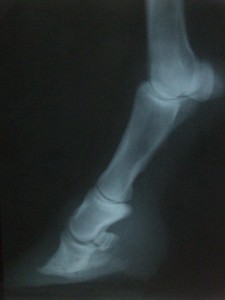

RTG Pravá přední (07.04.2008)